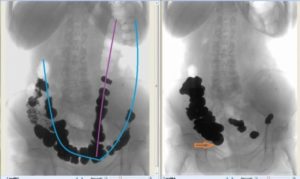

- Очень плотные каловые массы, которые имеют «каменистую» структуру – не удается размягчить содержимое кишечника. В таких случаях требуется консультация врача, который при необходимости назначит ректороманоскопию или колоноскопию с извлечением плотного содержимого под визуальным контролем при помощи специальных манипуляторов.

- Резкое снижение тонуса стенок толстой кишки с расширением диаметра просвета – патологическое состояние, которое сопровождается увеличением нижних отделов толстой кишки, часто имеет врожденное происхождение и называется мегаколон. При этом происходит скопление каловых масс, а после введения раствора достичь эффекта не удается.